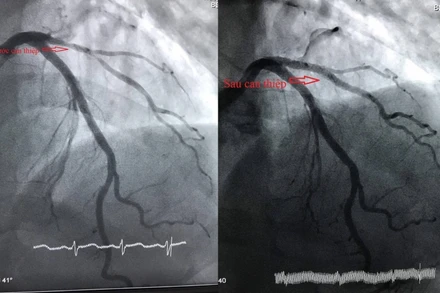

Ông W.Z., sinh năm 1971, quốc tịch Trung Quốc, tạm trú và làm việc tại huyện Long Hồ, tỉnh Vĩnh Long lên cơn đau ngực trái ngày càng tăng, chẩn đoán nhồi máu cơ tim cấp, được can thiệp mạch vành cứu sống kịp thời.